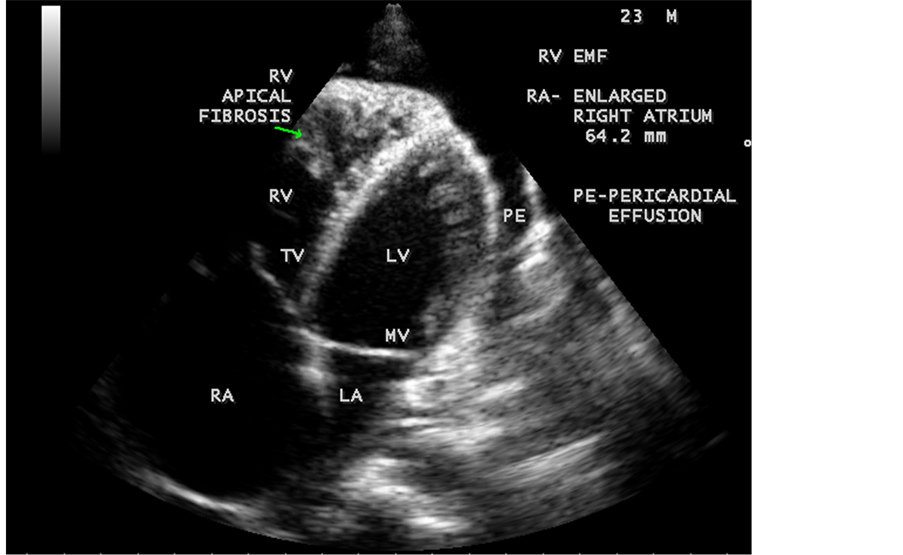

pressure 100/70 mmHg. Auscultation revealed diminished breath sounds on the right side of the chest with a dull note on percussion and a loud P2 (pulmonic component of second heart sound) with grade 2/6 soft systolic murmur over the lower left sternal border which increases in intensity with deep inspiration (Carvallo’s sign) suggesting tricuspid regurgitation. ECG revealed no arrhythmias and X-ray chest showed right- sided pleural effusion and extensive calcification over the cardiac shadow as shown in Figure 9. Transthoracic echocardiography revealed apical fibrosis of right ventricle, moderate pericardial effusion, right atrial dilatation as shown in Figure 10 and Figure 12, suggesting right ventricular endomyocardial fibrosis and severe tricuspid regurgitation as in Figure 11, Figure 13 and Figure 14 indicates coexisting pulmonary hypertension due to pulmonary damage caused by tuberculosis as shown in Figure 13 and free RV outflow tract as in Figure 15. Patient was treated with antituberculous drugs, antifailure measures such as digoxin and diuretics, ascites fluid tapping and antibiotics. He showed mild improvement in his symptoms.

Figure 11. Apical four chamber view suggesting RV (right ventricular) apical fibrosis, RA dilatation and severe tricuspid regurgitation suggesting right ventricular endomyocardial fibrosis with an extension of fibrosis in the LV apex.

Figure 12. Apical four chamber view showing the RV apical fibrosis with mild pericardial effusion in a 23-year-old male with tuberculosis.